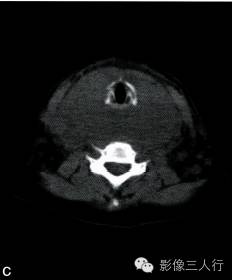

A~C.CT平扫横断面;D~F. CT增强横断面;G. HE×40

双侧甲状腺、颌下腺及咽淋巴环见多发结节融合状软组织影,边界不清,可见包膜,病灶密度欠均匀,内可见线样分隔,未见明显坏死及钙化,双颈各区可见大小不等的淋巴结,边界欠清,密度较均匀(图A~C)。增强横断面(图D~F)扫描双侧甲状腺、颌下腺及咽淋巴环病灶包膜及分隔可见明显强化,双颈淋巴结可见较明显强化。